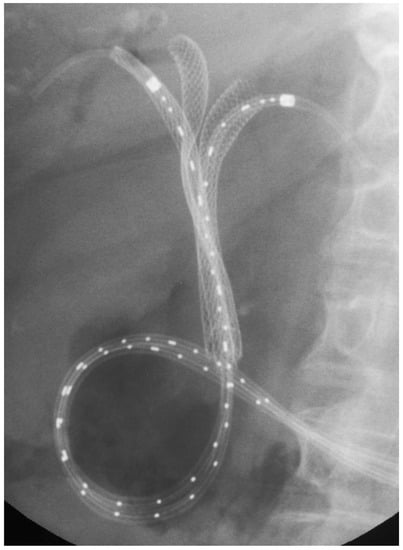

- Kongkam, P.; Tasneem, A.A.; Rerknimitr, R. Combination of endoscopic retrograde cholangiopancreatography and endoscopic ultrasonography-guided biliary drainage in malignant hilar biliary obstruction. Dig. Endosc. 2019, 31, 50–54. [Google Scholar] [CrossRef] [PubMed]

- Park, D.H. Endoscopic ultrasound-guided biliary drainage of hilar biliary obstruction. J. Hepato-Biliary-Pancreat. Sci. 2015, 22, 664–668. [Google Scholar] [CrossRef]

- Park, S.J.; Choi, J.-H.; Park, D.H.; Choi, J.H.; Lee, S.S.; Seo, D.-W.; Lee, S.K.; Kim, M.-H. Expanding indication: EUS-guided hepaticoduodenostomy for isolated right intrahepatic duct obstruction (with video). Gastrointest. Endosc. 2013, 78, 374–380. [Google Scholar] [CrossRef]